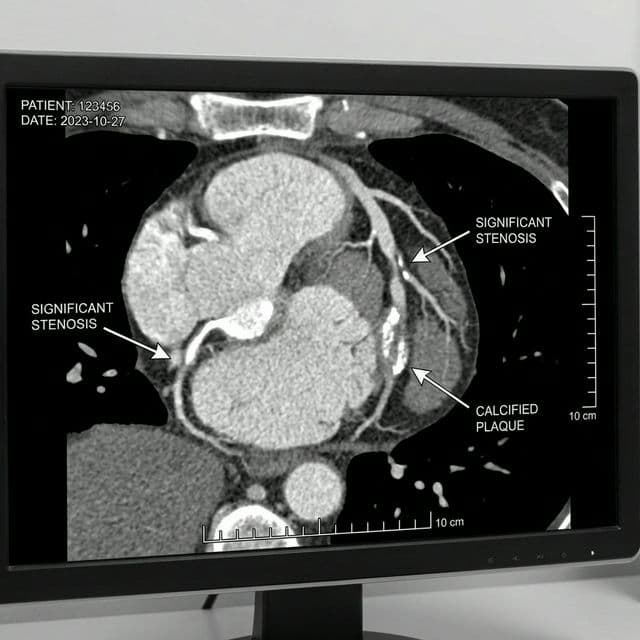

Positive — Disease DetectedURGENT

Input — CT Coronary Angiogram

CT CORONARY ANGIOGRAM⚠ ABNORMAL

CARD-2026-0113-001MedVision AI v3.2

| Impression | “Significant multi-vessel coronary artery disease with triple-vessel involvement and concurrent left ventricular hypertrophy. High-risk coronary anatomy requiring cardiology evaluation for potential revascularization. Aggressive secondary prevention measures indicated.” |

| Performance | Confidence: 9/10 · Analysis: 3.8s · Agreement: 91% |

| Remarks | This cardiac CT angiogram reveals significant multi-vessel coronary artery disease with evidence of left ventricular hypertrophy, likely secondary to chronic hypertension. The findings warrant urgent cardiology consultation for consideration of invasive coronary angiography and potential revascularization. |

Findings (8)

Significant stenosis (70-75%) of the proximal left anterior descending artery with mixed plaque composition

Moderate stenosis (50-60%) of the mid left circumflex artery

Moderate stenosis (60-65%) of the proximal right coronary artery with calcified plaque

Concentric left ventricular hypertrophy with septal wall thickness of 14mm

Preserved left ventricular ejection fraction (55-60%)

No evidence of pericardial effusion

Normal ascending aorta diameter (3.8cm)

Coronary artery calcium score consistent with high cardiovascular risk